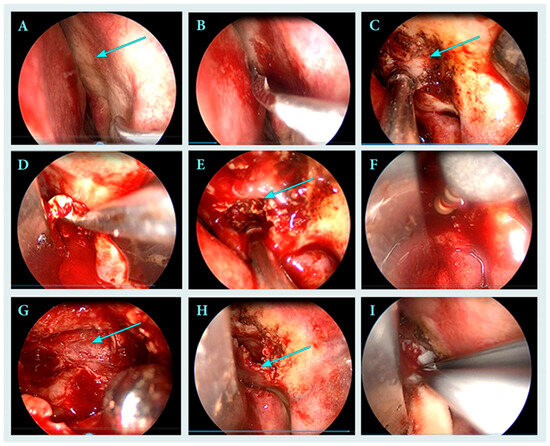

►▼

The study reports a diagnostic challenge involving an inflammatory lesion mimicking a brown tumor. A 23-year-old male patient was referred for treatment of a cystic lesion in the left frontal process of the maxilla and ethmoid region. The leading symptoms were hemoptysis and

The study reports a diagnostic challenge involving an inflammatory lesion mimicking a brown tumor. A 23-year-old male patient was referred for treatment of a cystic lesion in the left frontal process of the maxilla and ethmoid region. The leading symptoms were hemoptysis and chronic sinus inflammation. Endoscopic surgery was performed under general anesthesia, including curettage and drainage of the lesion into the middle nasal meatus. Histopathological examination revealed chronic inflammatory and fibrotic changes with hemosiderin deposits and CD68(+) histiocytes, findings that could suggest a brown tumor. However, subsequent laboratory investigations excluded this diagnosis. Postoperative healing was uneventful, with complete resolution of symptoms. This report highlights the importance of distinguishing inflammatory from metabolic bone lesions in the paranasal sinuses and underscores the critical role of histopathological evaluation in differentiating true neoplasms from inflammatory pseudotumors.

Figure 1